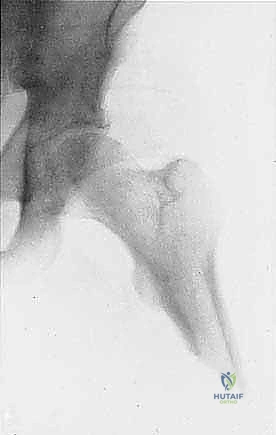

بتر الفخذ فوق الركبة (Transfemoral Amputation)، أو ما يُعرف اختصارًا بـ (AKA)، هو إجراء جراحي جذري يتم فيه إزالة جزء من الساق بما في ذلك مفصل الركبة بأكمله، بحيث يتبقى جزء من عظم الفخذ ليكون هو الدعامة الأساسية للطرف المتبقي. في السياق الأورامي (Oncological Context)، يكون الهدف الأساسي والأهم من هذا البتر هو استئصال ورم خبيث (سرطان) ينمو بشراسة في عظم الفخذ أو الأنسجة الرخوة المحيطة به.

يتم اللجوء إلى هذا الخيار عندما يتبين طبياً أن الورم لا يمكن علاجه بطرق أخرى مثل الجراحة المحافظة على الأطراف (Limb Salvage Surgery)، أو عندما يفشل العلاج الكيميائي والإشعاعي في السيطرة على حجم الورم، أو عندما يكون الورم قد غزا الأوعية الدموية والأعصاب الرئيسية المغذية للطرف السفلي بشكل يجعل الحفاظ على الطرف خطراً على حياة المريض أو سبباً في طرف غير وظيفي ومؤلم.

- التصوير بالرنين المغناطيسي (MRI): هو المعيار الذهبي لتقييم أورام العظام والأنسجة الرخوة. يوضح للدكتور هطيف الامتداد الدقيق للورم داخل نخاع العظم ومدى غزو العضلات والأوعية الدموية المجاورة.